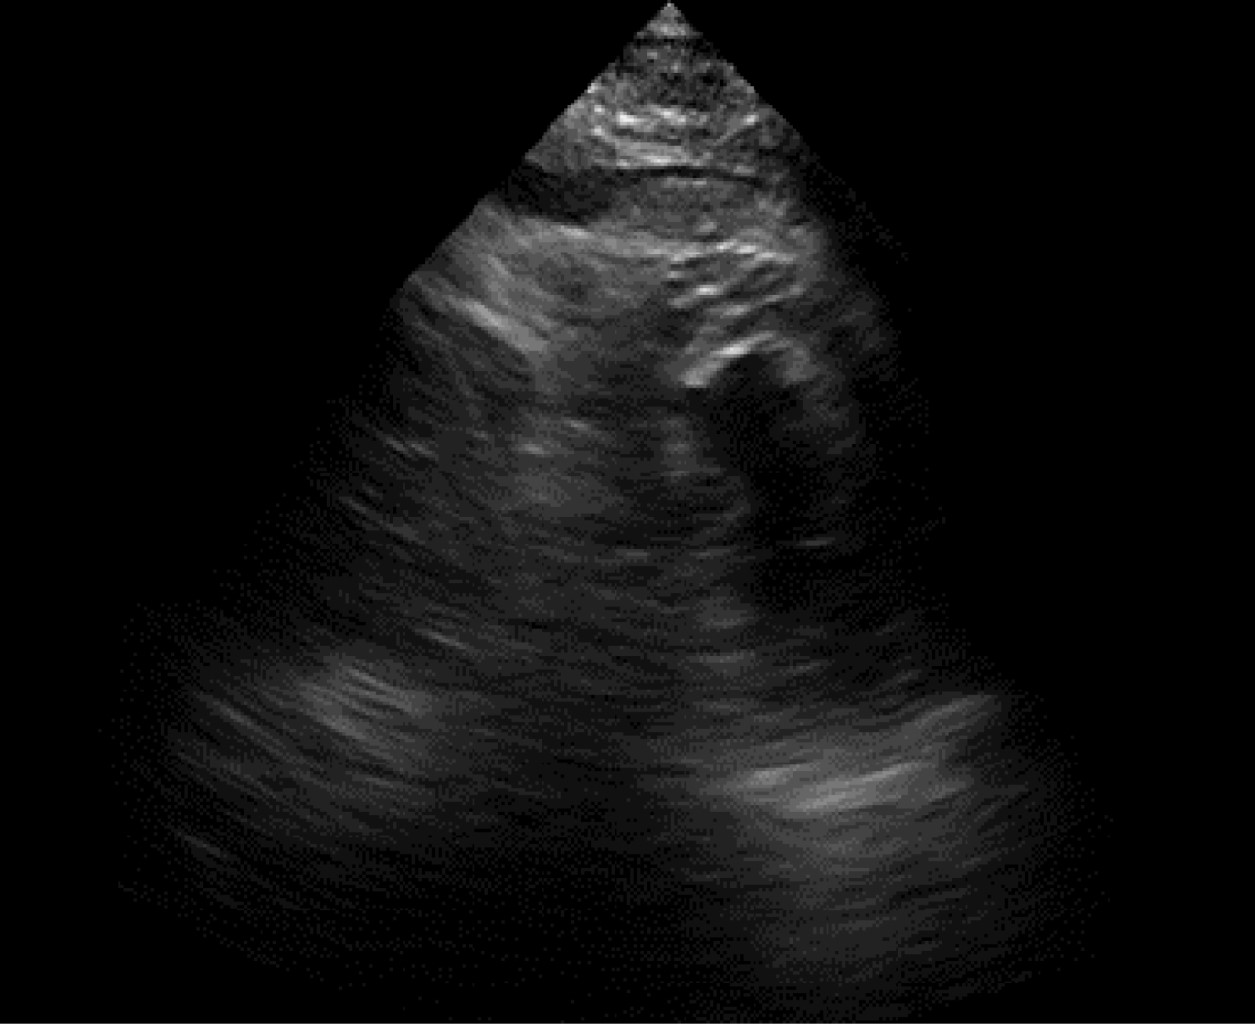

Ruptura cardiaca durante ecocardiograma de estrés con dobutamina como estratificación posterior a infarto agudo al miocardio

El ecocardiograma de estrés con dobutamina es ampliamente utilizado en la estratificación posterior a un infarto agudo al miocardio. Se han reportado complicaciones que pueden ser potencialmente mortales, siendo las arritmias ventriculares las más frecuentes. La ruptura cardiaca es una complicación rara, pero fatal. Se presenta el caso de un masculino de 68 años con un infarto inferior sin estrategia de reperfusión, el cual fue sometido a un ecocardiograma de estrés con dobutamina a los seis días del infarto. Durante la recuperación inicial el paciente presenta ruptura cardiaca por presencia de derrame pericárdico de aspecto hemático y disociación electro mecánica. Se realizó pericardiocentesis de urgencia, finalmente falleciendo el paciente. En la literatura se ha reportado el infarto inferior reciente y una zona discinética como las características de alto riesgo para presentarse. La selección adecuada del paciente, un ecocardiograma basal sin características de riesgo para ruptura y el tiempo de realización del estudio posterior al infarto puede disminuir la incidencia de esta complicación.

Figura 2